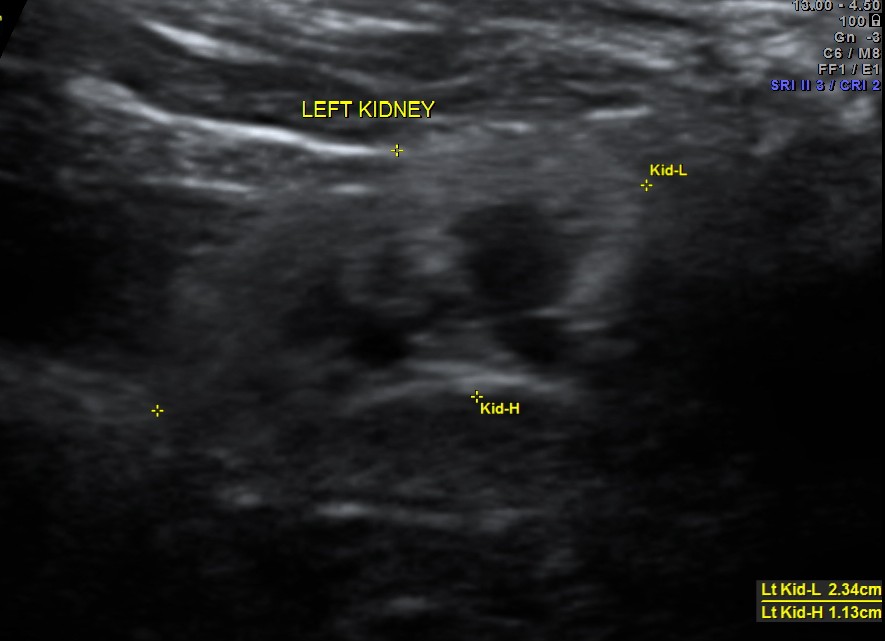

The following two pictures show the hyperechoic kidneys of the child with mild pelvi calyceal dilatation . The kidneys were picked up only with the 11 mhz transducer.